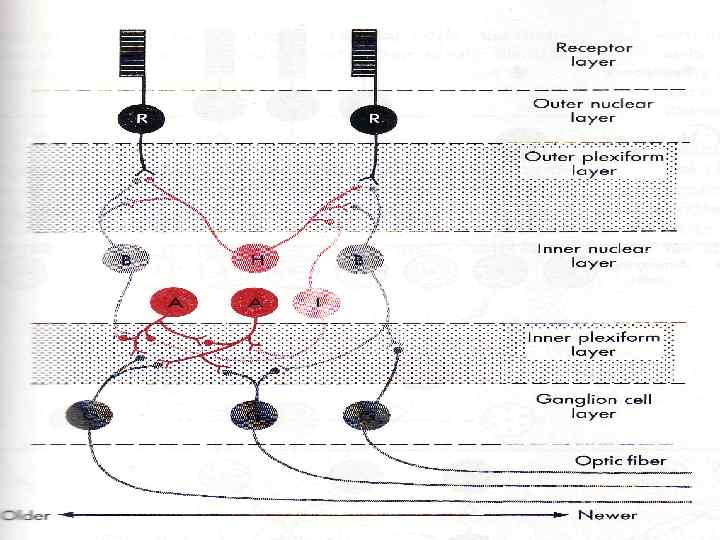

ПЕЙСМЕКЕР ТОЧНО НЕ УСТАНОВЛЕН ПРЕДПОЛОЖИТЕЛЬНО – клетки КАХАЛЯ (СЕТЬ МЕЖДУ СЛОЯМИ ГЛАДКИХ МЫШЦ)

ПЕЙСМЕКЕР ТОЧНО НЕ УСТАНОВЛЕН ПРЕДПОЛОЖИТЕЛЬНО – клетки КАХАЛЯ (СЕТЬ МЕЖДУ СЛОЯМИ ГЛАДКИХ МЫШЦ)

1906 cell structure of the nervous system Camillo Golgi Italy, 1843– 1926 Santiago Ramón y Cajal Spain, 1852– 1934

1906 cell structure of the nervous system Camillo Golgi Italy, 1843– 1926 Santiago Ramón y Cajal Spain, 1852– 1934